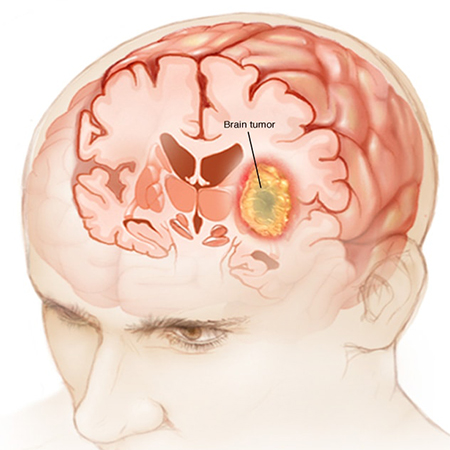

یکی دیگر از اختلالات غده صنوبری تومورهای پینه آل است که می تواند خوش خیم یا بدخیم باشد. تومورهای پینه آل می توانند علائم مختلفی از جمله سردرد، تهوع، استفراغ و مشکلات بینایی ایجاد کنند.

تومورهای پینه آل نوعی تومور مغزی هستند که می توانند در غده صنوبری، غده کوچک درون ریز واقع در مرکز مغز ایجاد شوند. بسته به اندازه، محل و نوع تومور، علائم تومور پینه آل می تواند بسیار متفاوت باشد. در اینجا برخی از علائم رایج تومورهای پینه آل وجود دارد:

•سردرد: تومورهای پینه آل می توانند باعث سردرد شوند که می تواند شدید و مداوم باشد. سردرد ممکن است در صبح بدتر شود و در طول روز بهبود یابد.

• مشکلات بینایی: تومورهای پینه آل می توانند باعث مشکلات بینایی شوند، مانند دوبینی، تاری دید ، یا از دست دادن بینایی در یک یا هر دو چشم.

• تهوع و استفراغ: تومورهای پینه آل می توانند باعث تهوع و استفراغ شوند که ممکن است در صبح بدتر شوند.

• تشنج: تومورهای پینه آل می توانند باعث تشنج شوند که اختلالات الکتریکی ناگهانی و کنترل نشده در مغز است که می تواند باعث تشنج، از دست دادن هوشیاری و سایر علائم شود.

• اختلالات خواب: تومورهای پینه آل می توانند چرخه خواب و بیداری را مختل کنند و باعث بی خوابی، خواب آلودگی مفرط یا سایر اختلالات خواب شوند.

• عدم تعادل هورمونی: تومورهای پینه آل می توانند تولید و تنظیم هورمون ها را مختل کنند و منجر به علائمی مانند اختلالات رشد ، بلوغ تاخیری یا بلوغ زودرس شوند.

• تغییرات رفتاری: تومورهای پینه آل می توانند باعث تغییراتی در رفتار و شخصیت، مانند تحریک پذیری، نوسانات خلقی یا افسردگی شوند.

توجه به این نکته مهم است که این علائم می تواند ناشی از شرایط دیگر نیز باشد و همه تومورهای پینه آل علائم ایجاد نمی کنند. اگر هر یک از این علائم را تجربه می کنید، مهم است که برای تشخیص و درمان مناسب با یک متخصص مراقبت های بهداشتی مشورت کنید.